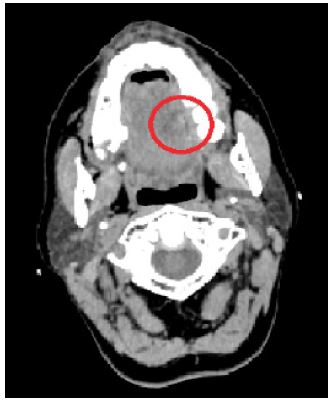

A 32-year-old male, with no previous medical history, was referred to the ENT Department due to lingual pain and oedema, which gradually worsened over the course of 48 hours. The patient was a non-smoker with no history of trauma and good oral hygiene. Palpation revealed a firm mass located in the anterior middle area of the tongue with spontaneous pus discharge streaming from its inferior surface. Rigid fiberoptic laryngoscopy revealed no pathology from the oropharynx and larynx. As for the laboratory tests, white blood cell (WBC) count and hsCRP were within normal rates, whereas the CT scan revealed soft tissue oedema of the middle line of the tongue with varying enhancement and air accumulation (Figure 3). The patient was admitted to the ENT Department and the abscess was drained under TIVA via an extension of the existing fistula (sublingual incision) (Figure 4). During hospitalization he received treatment with ampicillin/ sulbactam, metronidazole and anti-inflammatory agents i.v. empirically, as the pus culture obtained during surgery revealed no specific pathogen. The symptoms subsided after three days and the patient was discharged with oral antibiotic treatment.

Figure 3: Cervical CT: midline tongue lesion of varying enhancement and air accumulation (red circle).